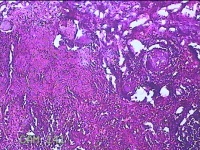

性别

男

年龄

32岁

临床诊断

1.急性化脓性阑尾炎并穿孔 2.弥漫性腹膜炎

一般病史

转移性右下腹疼痛1天。

标本名称

阑尾

大体所见

灰白暗红色阑尾4.8x1.3x0.7cm一条,表面糜烂,肿胀,带少许系膜,切断阑尾,见腔内暗红色。